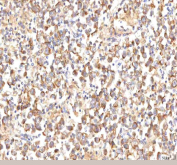

IHC staining of FFPE human liver cancer tissue with MANSC4 antibody. HIER: boil tissue sections in pH8 EDTA for 20 min and allow to cool before testing.

IHC staining of FFPE human testicular seminoma tissue with MANSC4 antibody. HIER: boil tissue sections in pH8 EDTA for 20 min and allow to cool before testing.